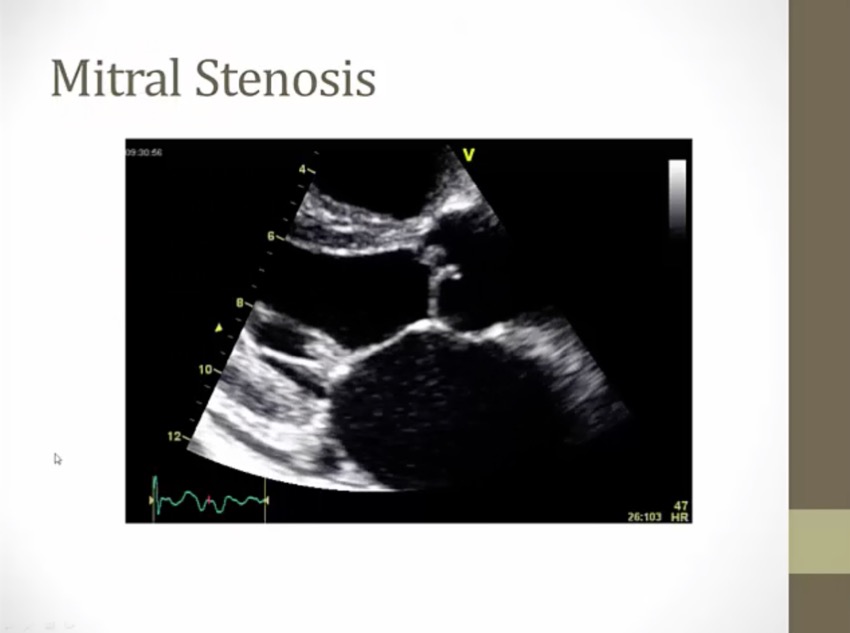

Mitral Stenosis

ventricle normal but just less blood

hemoptysis: very high pressure in lung

afib: dilated atrium due to volume overload, complication = stroke

mitral valve in middle can't open